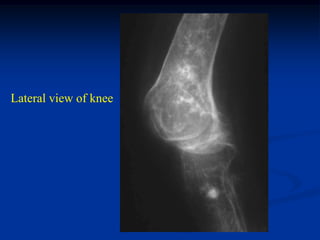

71 year female with Ollier’s left lower extremity

Lateral view of knee

Photomic

Failure following

resurfacing TKA

because of loosening

Post op x-ray with constrained

TKA